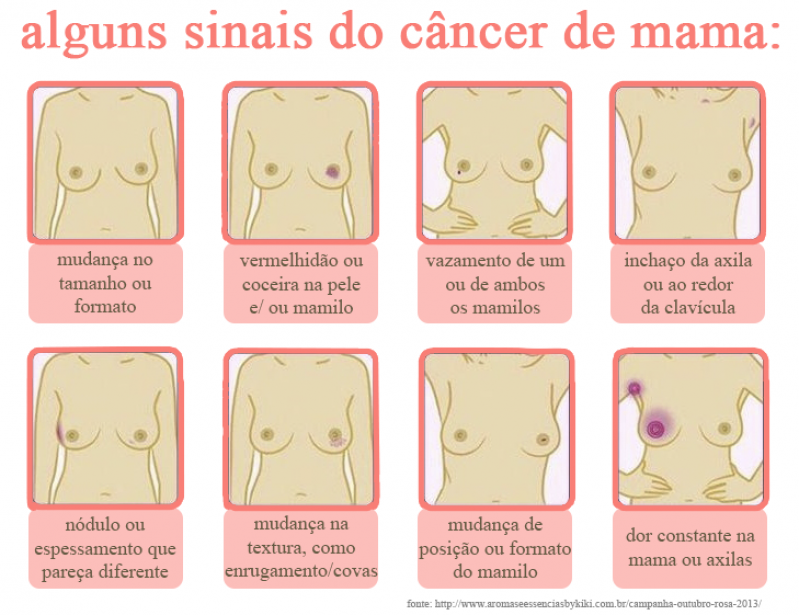

médico especialista mama perto Vila Nova Conceição atua para prevenir, diagnosticar, tratar e reabilitar pacientes com câncer de mama. Apenas o autoexame não é suficiente para perceber o surgimento de doenças na região. Sendo assim, o procedimento deve ser realizado por um profissional para garantir qualidade e eficiência no diagnóstico e tratamento.